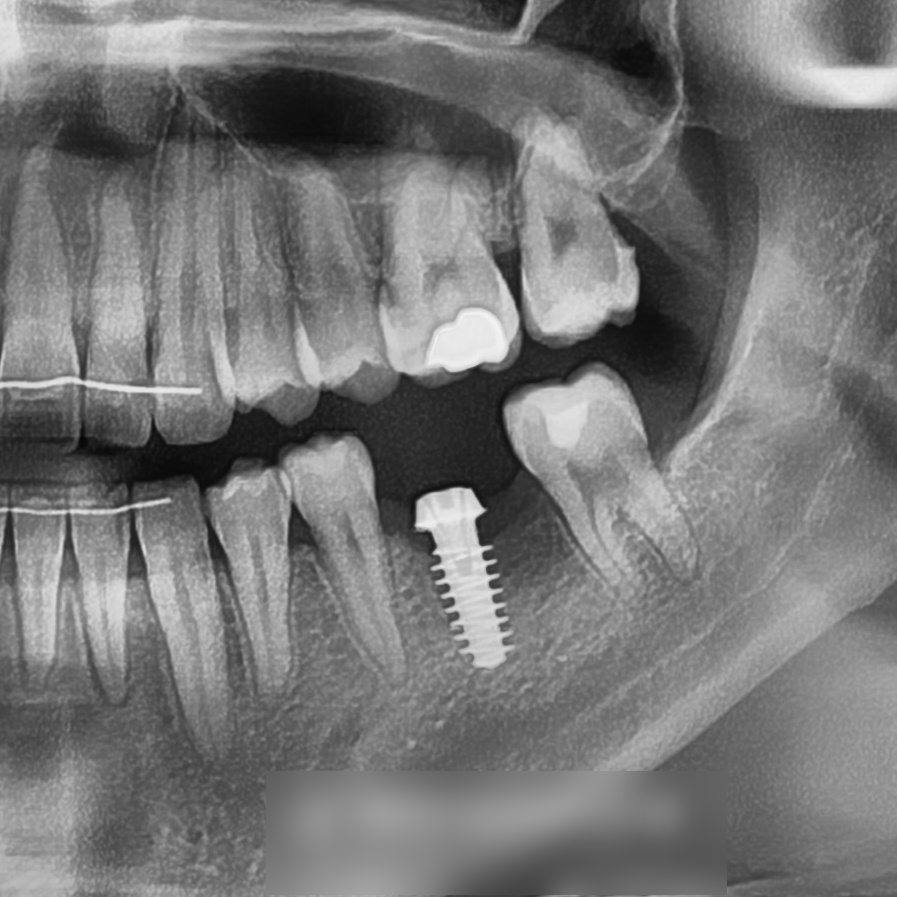

촬영일 : 23.12.04

엑스레이를 통해 부러진 어금니의

잔존 치질이 거의 없는 상태라는 점도 확인되었고,

보존치료가 어려워 발치가 필요한 것으로

판단되었습니다.

교정 종료 시점에서는

어금니 부위에 임플란트 를 심어진 모습입니다.